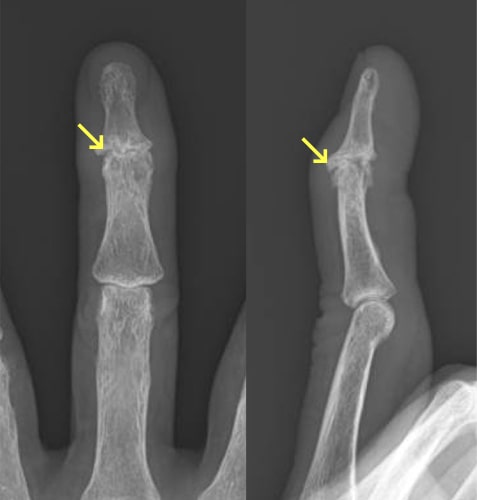

指骨・中手骨骨折

指骨・中手骨骨折写真

基節骨変形癒合により指交差現象が出現

(握ると環指が小指に重なる)

原因

壁を殴ってしまったり、転倒した際に強打してしまったりして生じます。

症状

手や指が腫れて、痛くて動かせなくなります。変形を認める場合もあります。

治療方針

転位やズレの程度で治療方針を決めます。指の骨折の治療で重要なことは長期間固定をして拘縮を作らないことです。ほんの数週間の外固定により骨折部以外の関節も固くなってしまい、また少しの変形であっても指を握った時に重なったりする重篤な後遺症が生じることがありますので注意が必要です。手外科専門医にかかることをお勧めします。